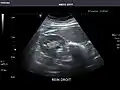

Liver -